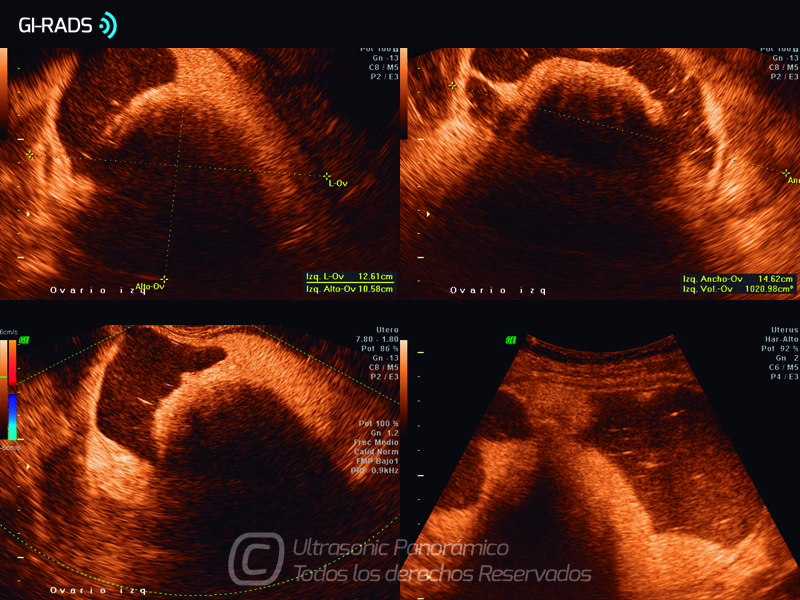

Patologías Benignas – Teratoma Maduro

• Patologías Benignas – Teratoma Maduro